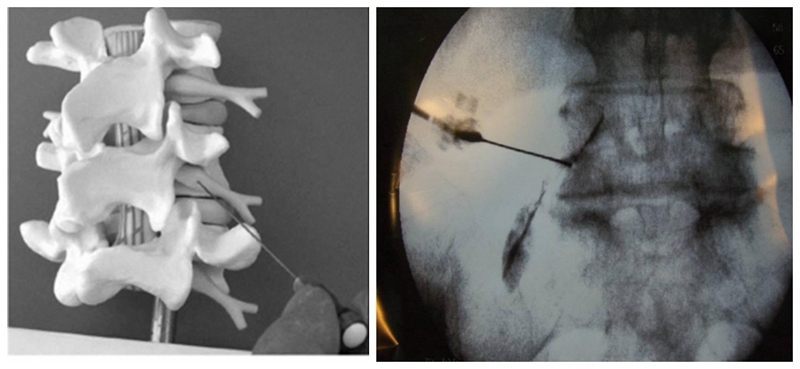

图1

解决了注射药物的问题,下一步需要解决的便是注射的方法。采用何种注射方法更为有效安全?人们发现,经骶裂孔注射治疗坐骨神经痛通常需要注射50-60ml的较大剂量,其作用机制是通过药物弥散至病变部位而产生作用,因此,该注射方式并不像想象的那么安全。那么有没有其他的注射途径呢?能不能把药物直接注射到炎症受压的神经根上呢?这是一种最直接而朴素的想法,很快就有人付之于实践,并把这种方法称之为Retro-neural approach(RN)入路。

图3

RN入路注射又可分为两种方式,即神经根鞘膜内注射(intra-epineuralinjection)和神经根周围注射(intra-epineuralinjection)。通过造影剂注射可以区分这两种不同的方法,当针尖进入神经根鞘膜内时,会获得神经根内羽毛状神经纤维的显影,而针尖在神经根周围时,造影剂会显示神经根的轮廓。

虽然RN入路可以解决注射方法的问题,然而其缺点同样明显,即该方法需要不断试错,在穿刺中,只用穿刺针碰触到病变神经根引起下肢疼痛时,医生才能确定穿刺的成功,因此这种方法具有一定的盲目性,也不可避免的会引起神经根的医源性损伤。